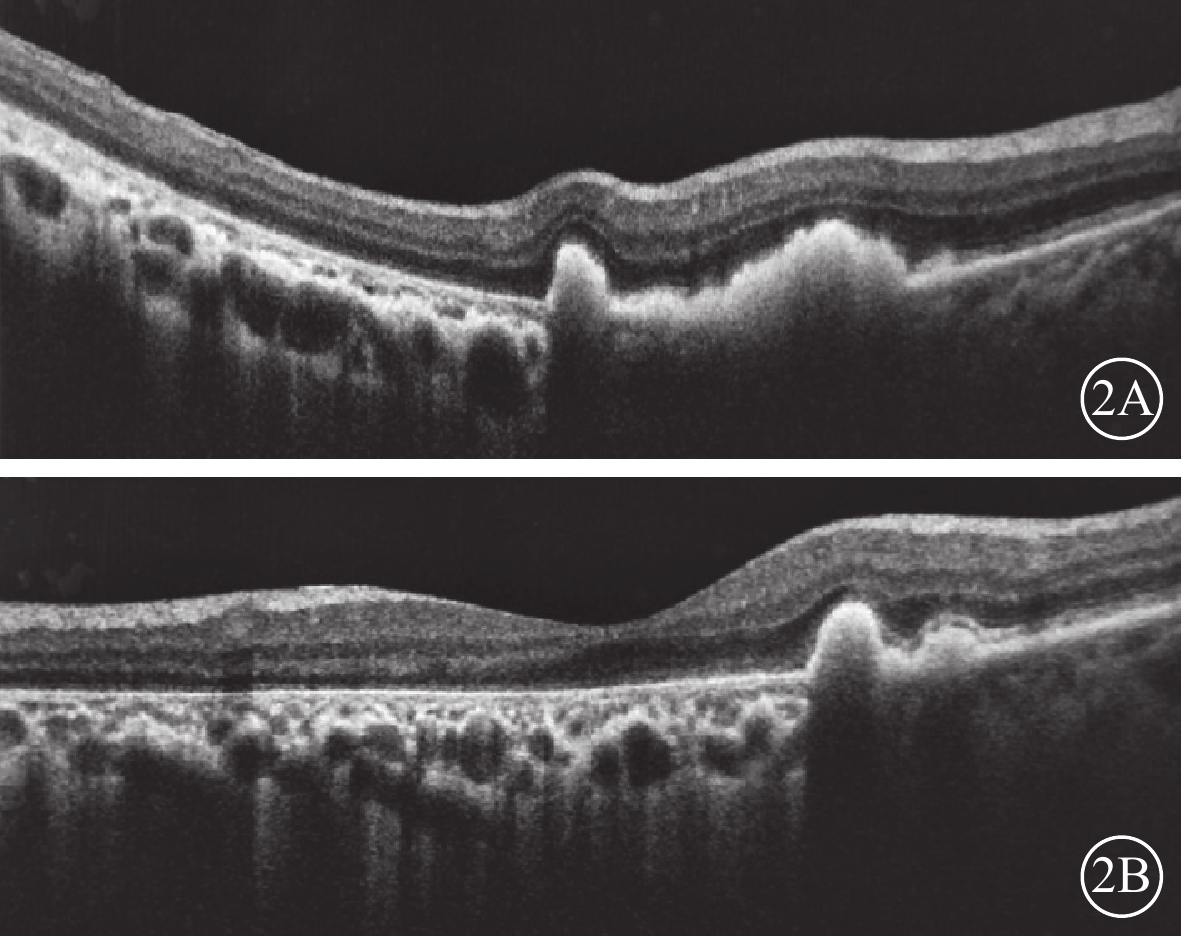

患者女,68歲。因雙眼視物模糊20 d于2018年3月20日來我院眼科就診。既往肺心病10年;否認雙眼外傷史,否認遺傳病家族史。眼部檢查:雙眼視力0.1,均不能矯正。右眼眼壓16 mmHg(1 mmHg=0.133 kPa),左眼眼壓15 mmHg。雙眼眼前節檢查正常。眼底檢查,雙眼后極部巨大RPE撕裂,撕裂區透見脈絡膜水腫;上方RPE收縮卷曲皺褶;視網膜血管紆曲(圖1)。OCT檢查,后極部撕裂區RPE信號消失。對應RPE卷曲皺褶處強反射隆起信號。未撕裂范圍RPE信號正常(圖2)。因患者原因未行FFA檢查。臨床診斷:雙眼特發性RPE撕裂。

圖2

雙眼OCT像。2A示右眼,卷曲的RPE呈隆起性強反射信號;2B示左眼,黃斑撕裂區RPE信號消失,脈絡膜水腫

圖2

雙眼OCT像。2A示右眼,卷曲的RPE呈隆起性強反射信號;2B示左眼,黃斑撕裂區RPE信號消失,脈絡膜水腫

患者女,68歲。因雙眼視物模糊20 d于2018年3月20日來我院眼科就診。既往肺心病10年;否認雙眼外傷史,否認遺傳病家族史。眼部檢查:雙眼視力0.1,均不能矯正。右眼眼壓16 mmHg(1 mmHg=0.133 kPa),左眼眼壓15 mmHg。雙眼眼前節檢查正常。眼底檢查,雙眼后極部巨大RPE撕裂,撕裂區透見脈絡膜水腫;上方RPE收縮卷曲皺褶;視網膜血管紆曲(圖1)。OCT檢查,后極部撕裂區RPE信號消失。對應RPE卷曲皺褶處強反射隆起信號。未撕裂范圍RPE信號正常(圖2)。因患者原因未行FFA檢查。臨床診斷:雙眼特發性RPE撕裂。

圖2

雙眼OCT像。2A示右眼,卷曲的RPE呈隆起性強反射信號;2B示左眼,黃斑撕裂區RPE信號消失,脈絡膜水腫

圖2

雙眼OCT像。2A示右眼,卷曲的RPE呈隆起性強反射信號;2B示左眼,黃斑撕裂區RPE信號消失,脈絡膜水腫